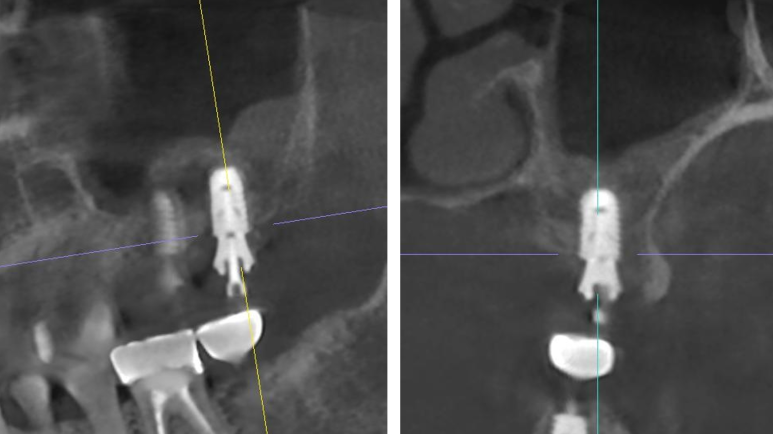

🦷 치료 대상: 상악 제1·2대구치 부위

| 상악 제 1대구치 | 상악 제 2대구치 |

CT 촬영 결과,

해당 부위는 골 높이 3~5mm 수준으로,

단순 식립만으로는 충분한 고정력을 확보하기 어려웠습니다.

다행히도:

- 상악동 점막이 건강하고

- 바닥(저부) 형태가 평탄하여

잇몸을 크게 절개하지 않는 수압 거상술로 접근하였습니다.